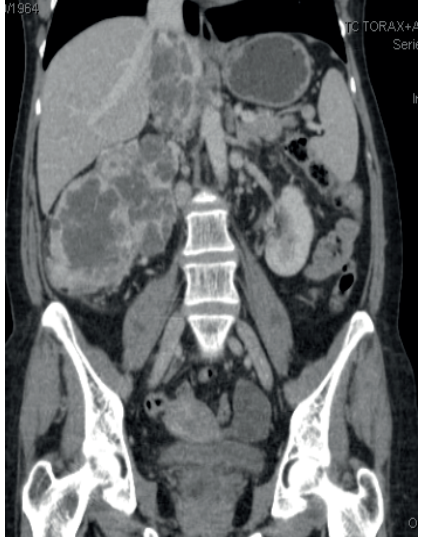

- A Tomografia Computadorizada (TC) de abdome e pelve com contraste é o padrão-ouro para diagnóstico e estadiamento.

- T1: Tumor ≤ 7 cm, restrito ao rim.

- T2: Tumor > 7 cm, restrito ao rim.

- T3: O tumor invade grandes veias ou o tecido perirrenal, mas não ultrapassa a fáscia de Gerota.

- T4: O tumor invade além da fáscia de Gerota ou a glândula adrenal ipsilateral.